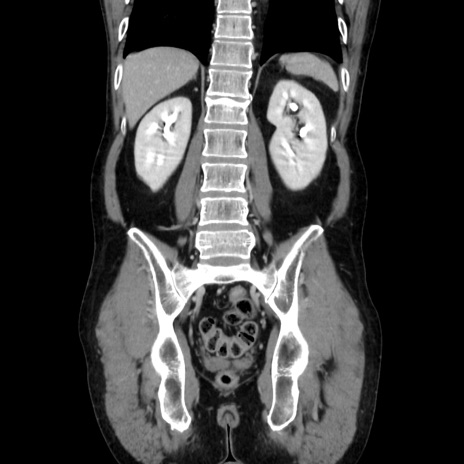

症例37(冠状断像)

【症例】40歳代 男性

【主訴】腹痛

【現病歴】4時間ほど前に電車に乗車中に臍部上より腹痛出現。徐々に増悪し起立困難となり、救急外来受診。生ものは数日食べていない。今朝お雑煮を食べた。

【身体所見】BT 36.8℃、BP 117/84mmHg、HR 91/min、SpO2 97%、苦悶様、腹部:臍上部広範囲圧痛あり、反跳痛±

【データ】WBC 8100、CRP 0.03

横断像